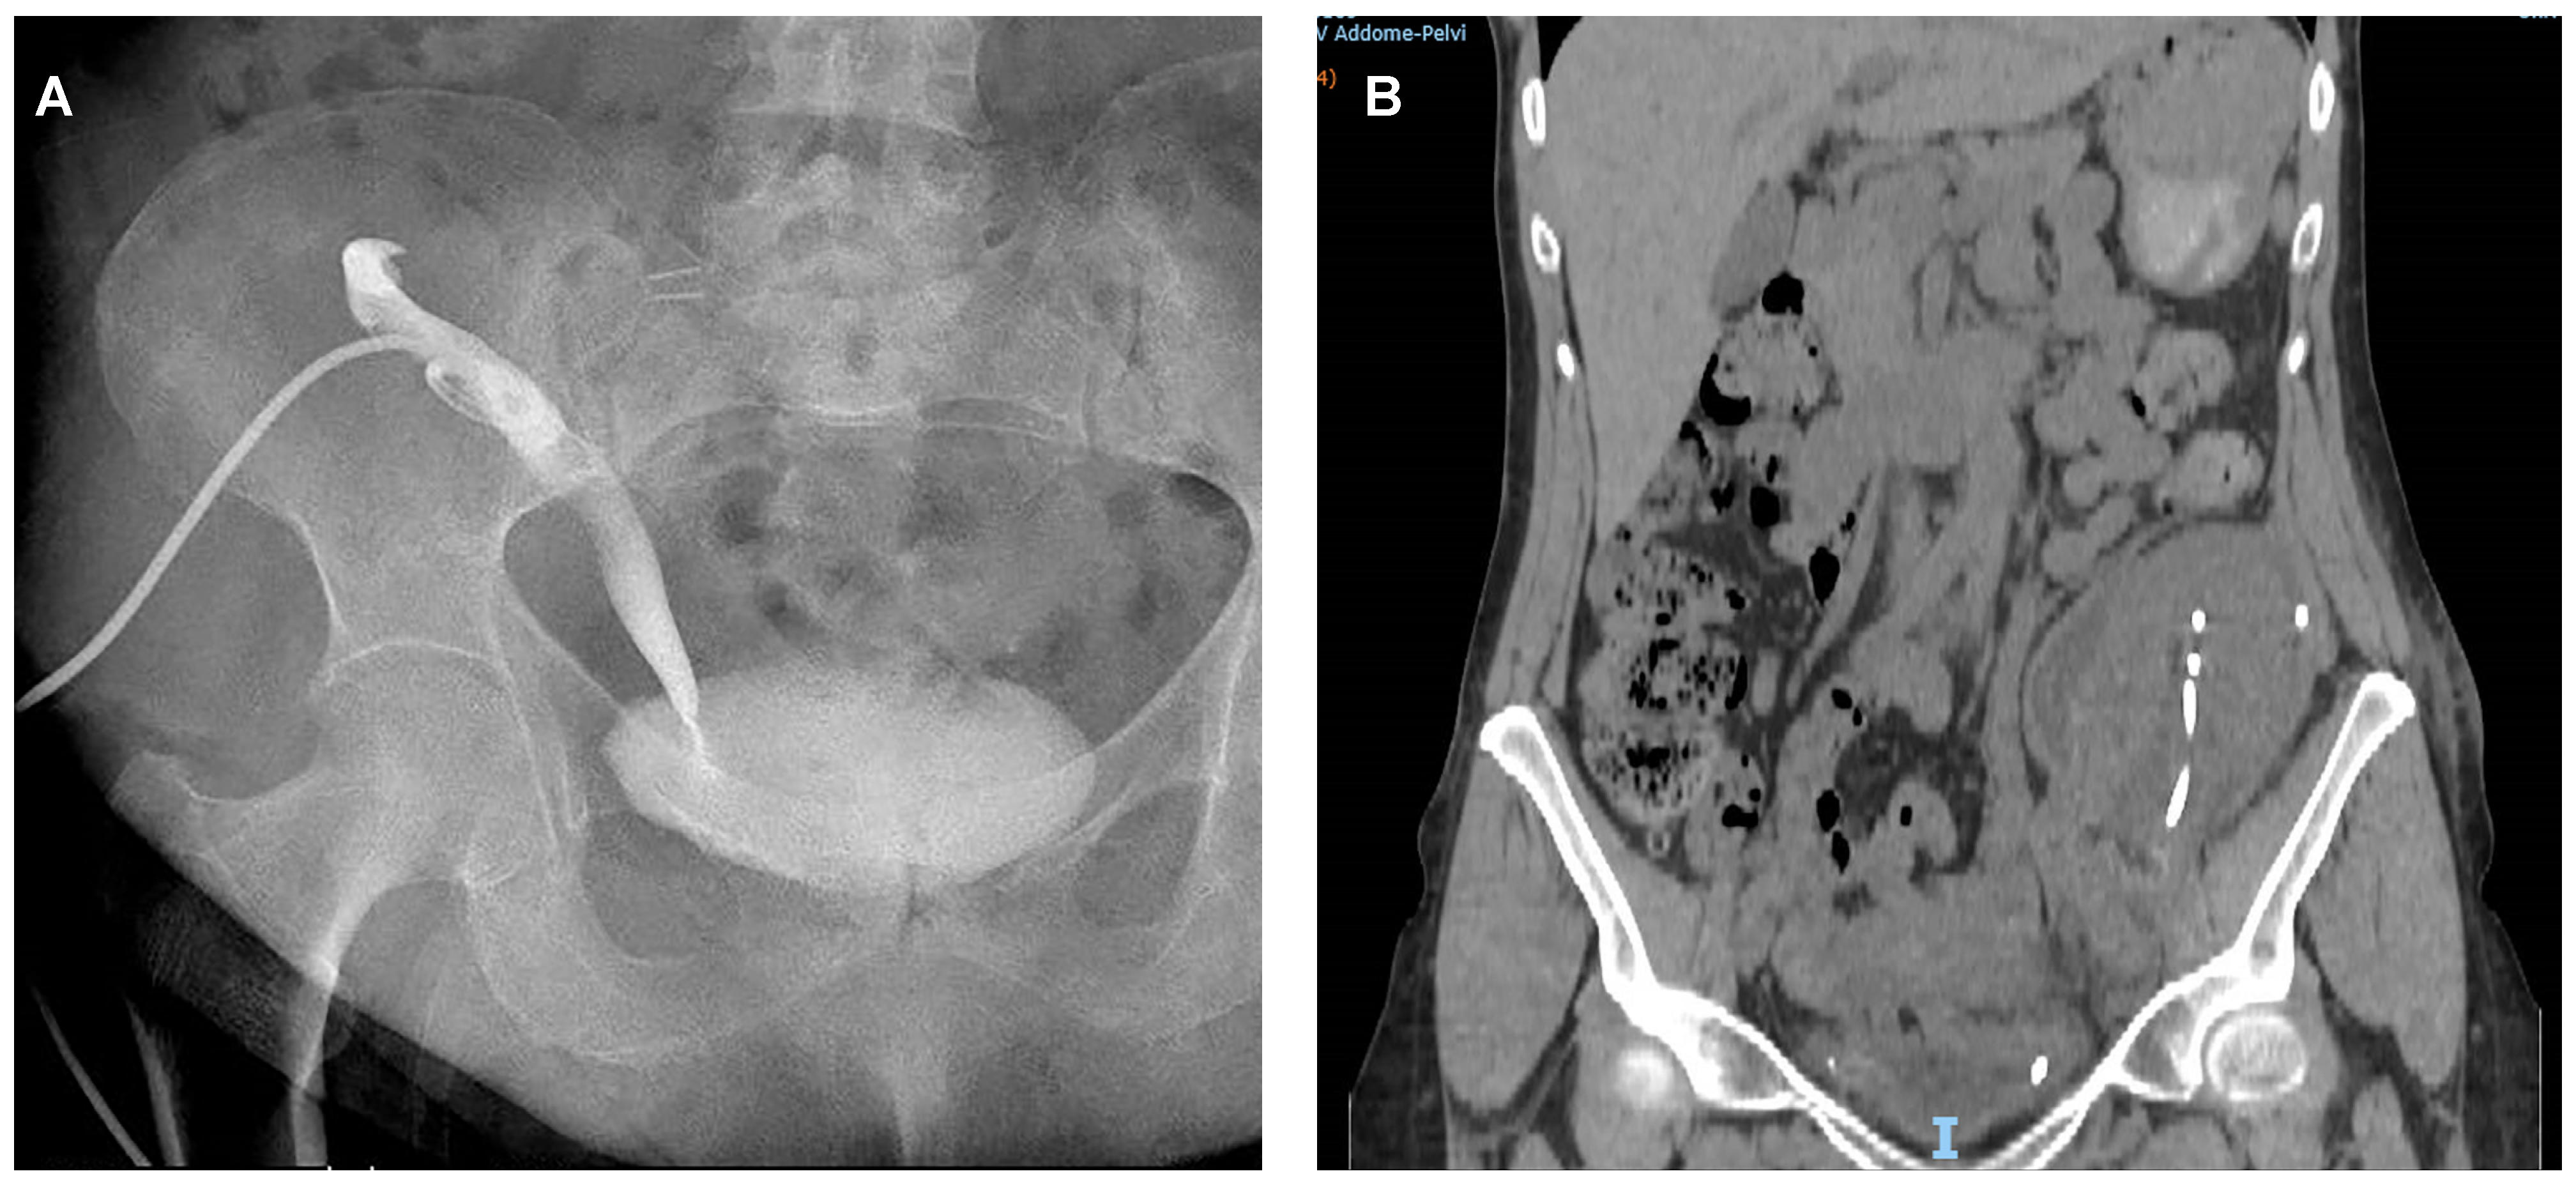

| Type of UC treatment: | |

| ● Nephrostomy + ureteral stenting | 17 (53.1%) |

| ● Cystoscopy + ureteral stenting | 3 (9.4%) |

| ● Nephrostomy | 2 (6.2%) |